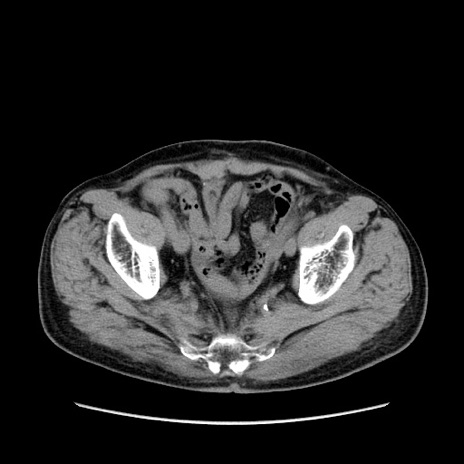

矢状断像